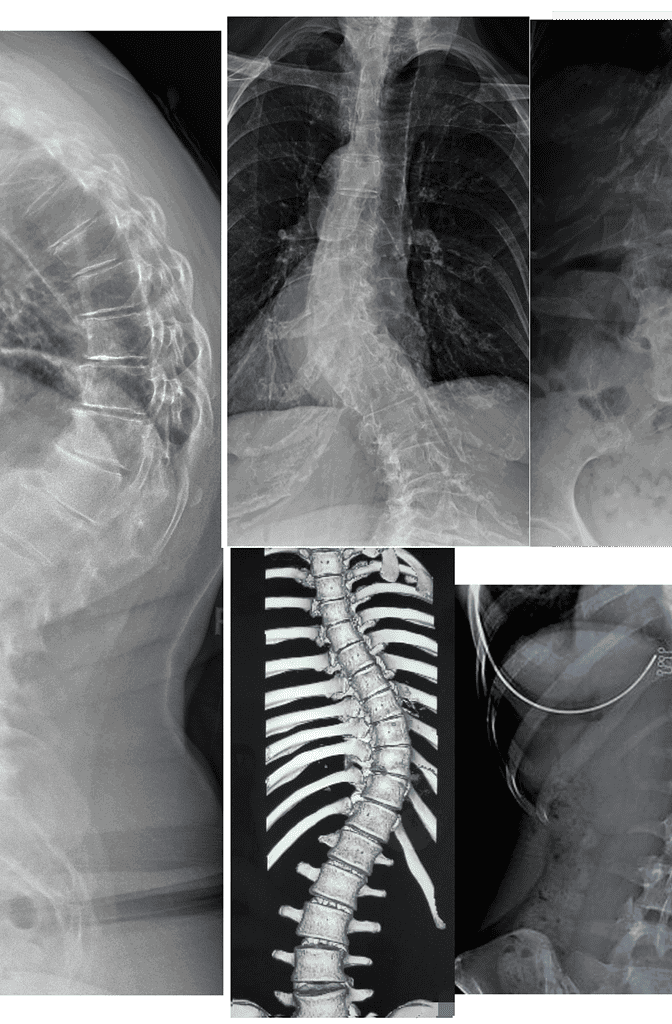

Real Results You Can Verify

Measurable outcomes on X-ray. Here is what our co-managed patients have experienced.

Note: Individual results vary. All measurements taken on calibrated standing AP radiographs by the treating doctor. Cases shown with patient/guardian consent.